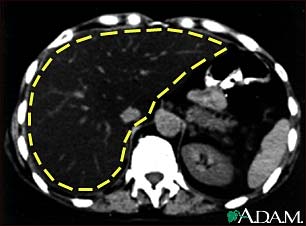

A CT scan of the upper abdomen showing a fatty liver (steatosis of the liver). Note the liver enlargement and dark color compared with the spleen (gray body in lower right).